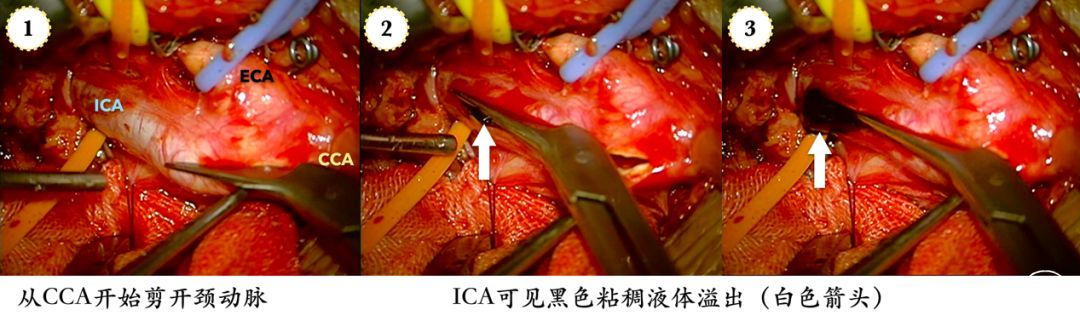

手术以复合手术的方式开始,常规暴露颈动脉,沿长轴剪开颈动脉。在ICA闭塞处溢出少量粘稠的黑色液体,这是尚未形成固体形态的血栓。

除黑色液体外,剩下的都是由粘稠、脆性较大的慢性血栓充填管腔。直视下,将微导管置入血栓,也就是ICA的管腔,向上走行没有阻力,微导管造影证实真腔后,留置微导丝。

在部分颈动脉缝合后,以侧壁钳夹闭剩余切口,手推造影显示ICA再通,但有明显的附壁血栓,采用网眼可控的Supera支架,完全覆盖血栓处,并在最后放开侧壁钳,以期将残留血栓碎屑冲出体外。